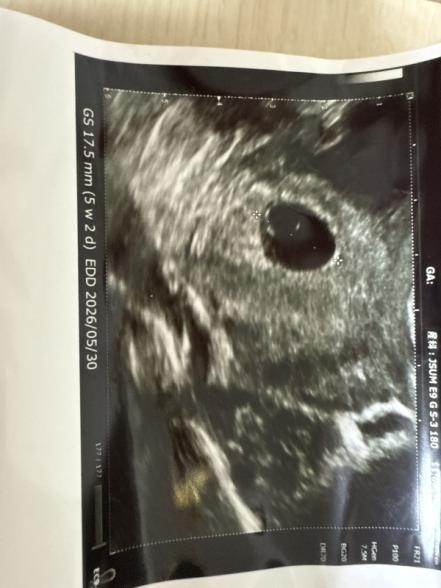

結果は赤ちゃんの姿が見えない。卵黄囊が大きい。稽留流産の可能性がある。との事でした。

胎嚢の大きさは17.5mmで5週くらいの大きさと言われました。

卵黄囊は実際自分が定規で測ったところ7mmでした。